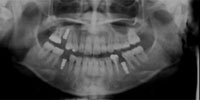

パノラマレントゲン写真

口内写真とパノラマレントゲンを撮影し、まずは顎の骨の状態まで詳しく確認しました。.

・歯がない期間が長く続いたため隣の歯が横に倒れてしまい、歯と歯との間に隙間が2ケ所できてしまっていた。

歯がない期間が長く続いたため隣の歯が横に倒れてしまい、歯と歯との間に隙間が2ケ所できてしまっていたため、インプラントの前に矯正治療で隙間をなくす治療を行う